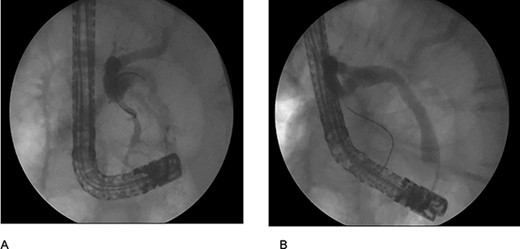

The patient was staged as ‘high risk’ according to the 2019 guidelines of American Society for Gastrointestinal Endoscopy risk classification guidelines for choledocholithiasis. The decision to perform an ERCP was taken, where an obstructive PDD was identified (Fig. 1). An absence of stones or biliary tumors was recognized (Fig. 2B) Oddi’s sphincterotomy and balloon sweep were performed, obtaining a control cholangiography without filling defects (Fig. 2). The initial presumptive diagnosis of choledocholithiasis was ruled out and a diagnosis of LS wasdone.

(A) cholangiography shows the bile duct with an extrinsic compression by the duodenal diverticulum witch conditions an angulation; (B) cholangiography after use the retrieval ballon catheter shows absence of stones.